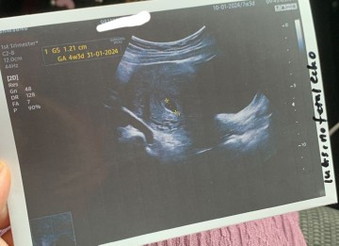

Hi mommy to be. Nak tanya korangg . Semalam saya pergi scan dkt swasta dan sptutnya kandungan saya 7w 3d tapi bila scan baru 4w 3d. Doc cakap salah satu faktor jdi mcm tu sbb tak tally dgn kiraan period sebab period tak teratur . Tapi kantung comel elok je doc ckp. Doc suruh repeat scan 2minggu lg. So saya nak tanya patut ke saya pergi kk untuk sahkan sbb kk kan dah boleh buka buku 8w ke ats? Sebab ada dgr kes kdg swasa dgn kk tak tally . Boleh bagi pendapat? First time pregnant. Thank you semua